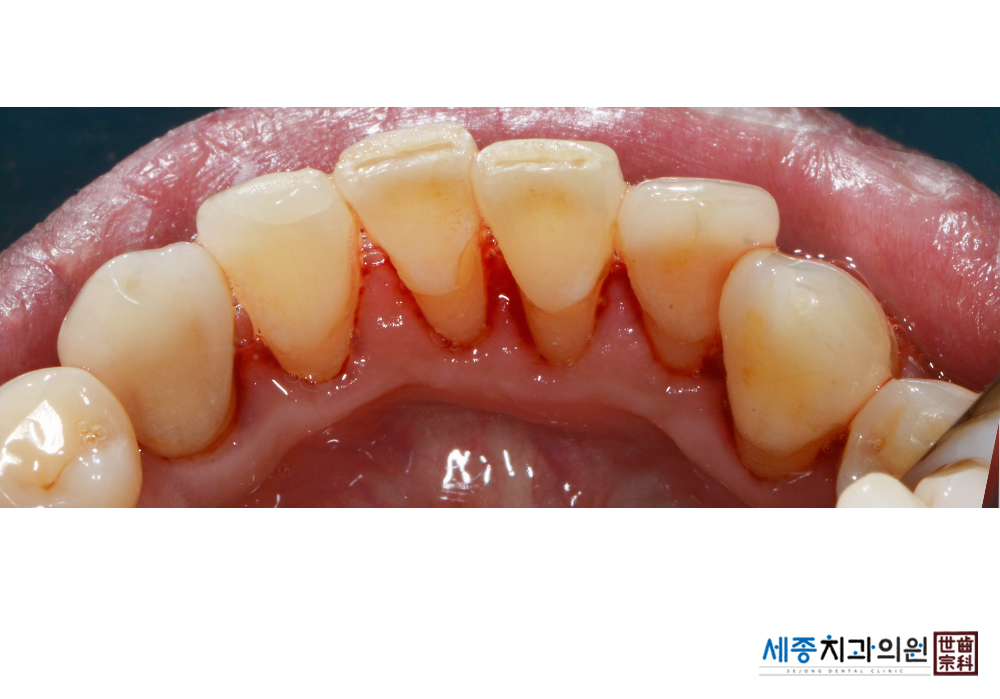

[스케일링] 치주질환 예방 스케일링

치료후 : 2020-01-17

가글마취&저주파 스켈러를 사용한 스케일링